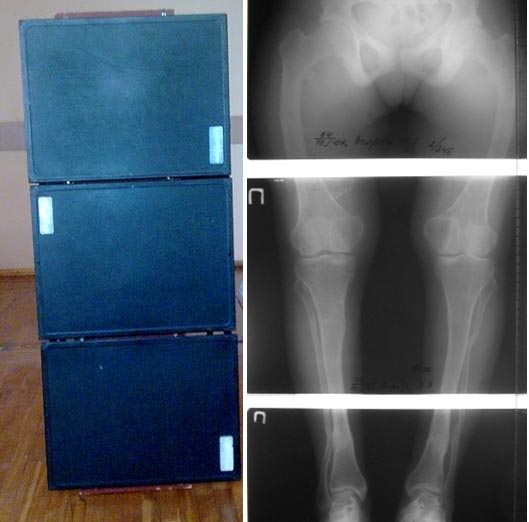

Вот таким образом? Точность оценки оси после склеивания пленок с

оставлением "зазора" между ними невысока. И часто на "зазор" приходится

щель коленного сустава